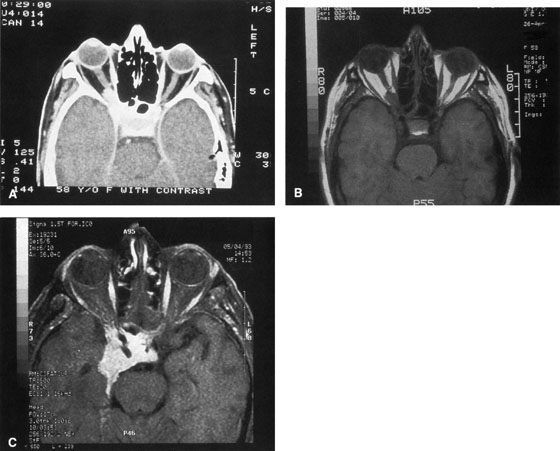

Figure 10. A. Large, well-encapsulated intraconal mass on MR scan. B. Small lateral canthotomy incision will be used to perform lateral orbitotomy and remove the intraconal mass.

Fig. 11. A. Lateral canthotomy incision is made with straight iris scissors. B. Periosteum is elevated off of the lateral orbital rim. C. Wide undermining allows retraction of the skin incision to permit superior and inferior osteotomies to be made with the air-driven saw. D. The bony rim has been outfractured. Because of the distensibility of the skin, it is possible to remove a large bone flap through the small canthotomy incision. E. The intraconal mass is extracted with the aid of the cryoprobe. F. The bone fragment is positioned for resuturing.